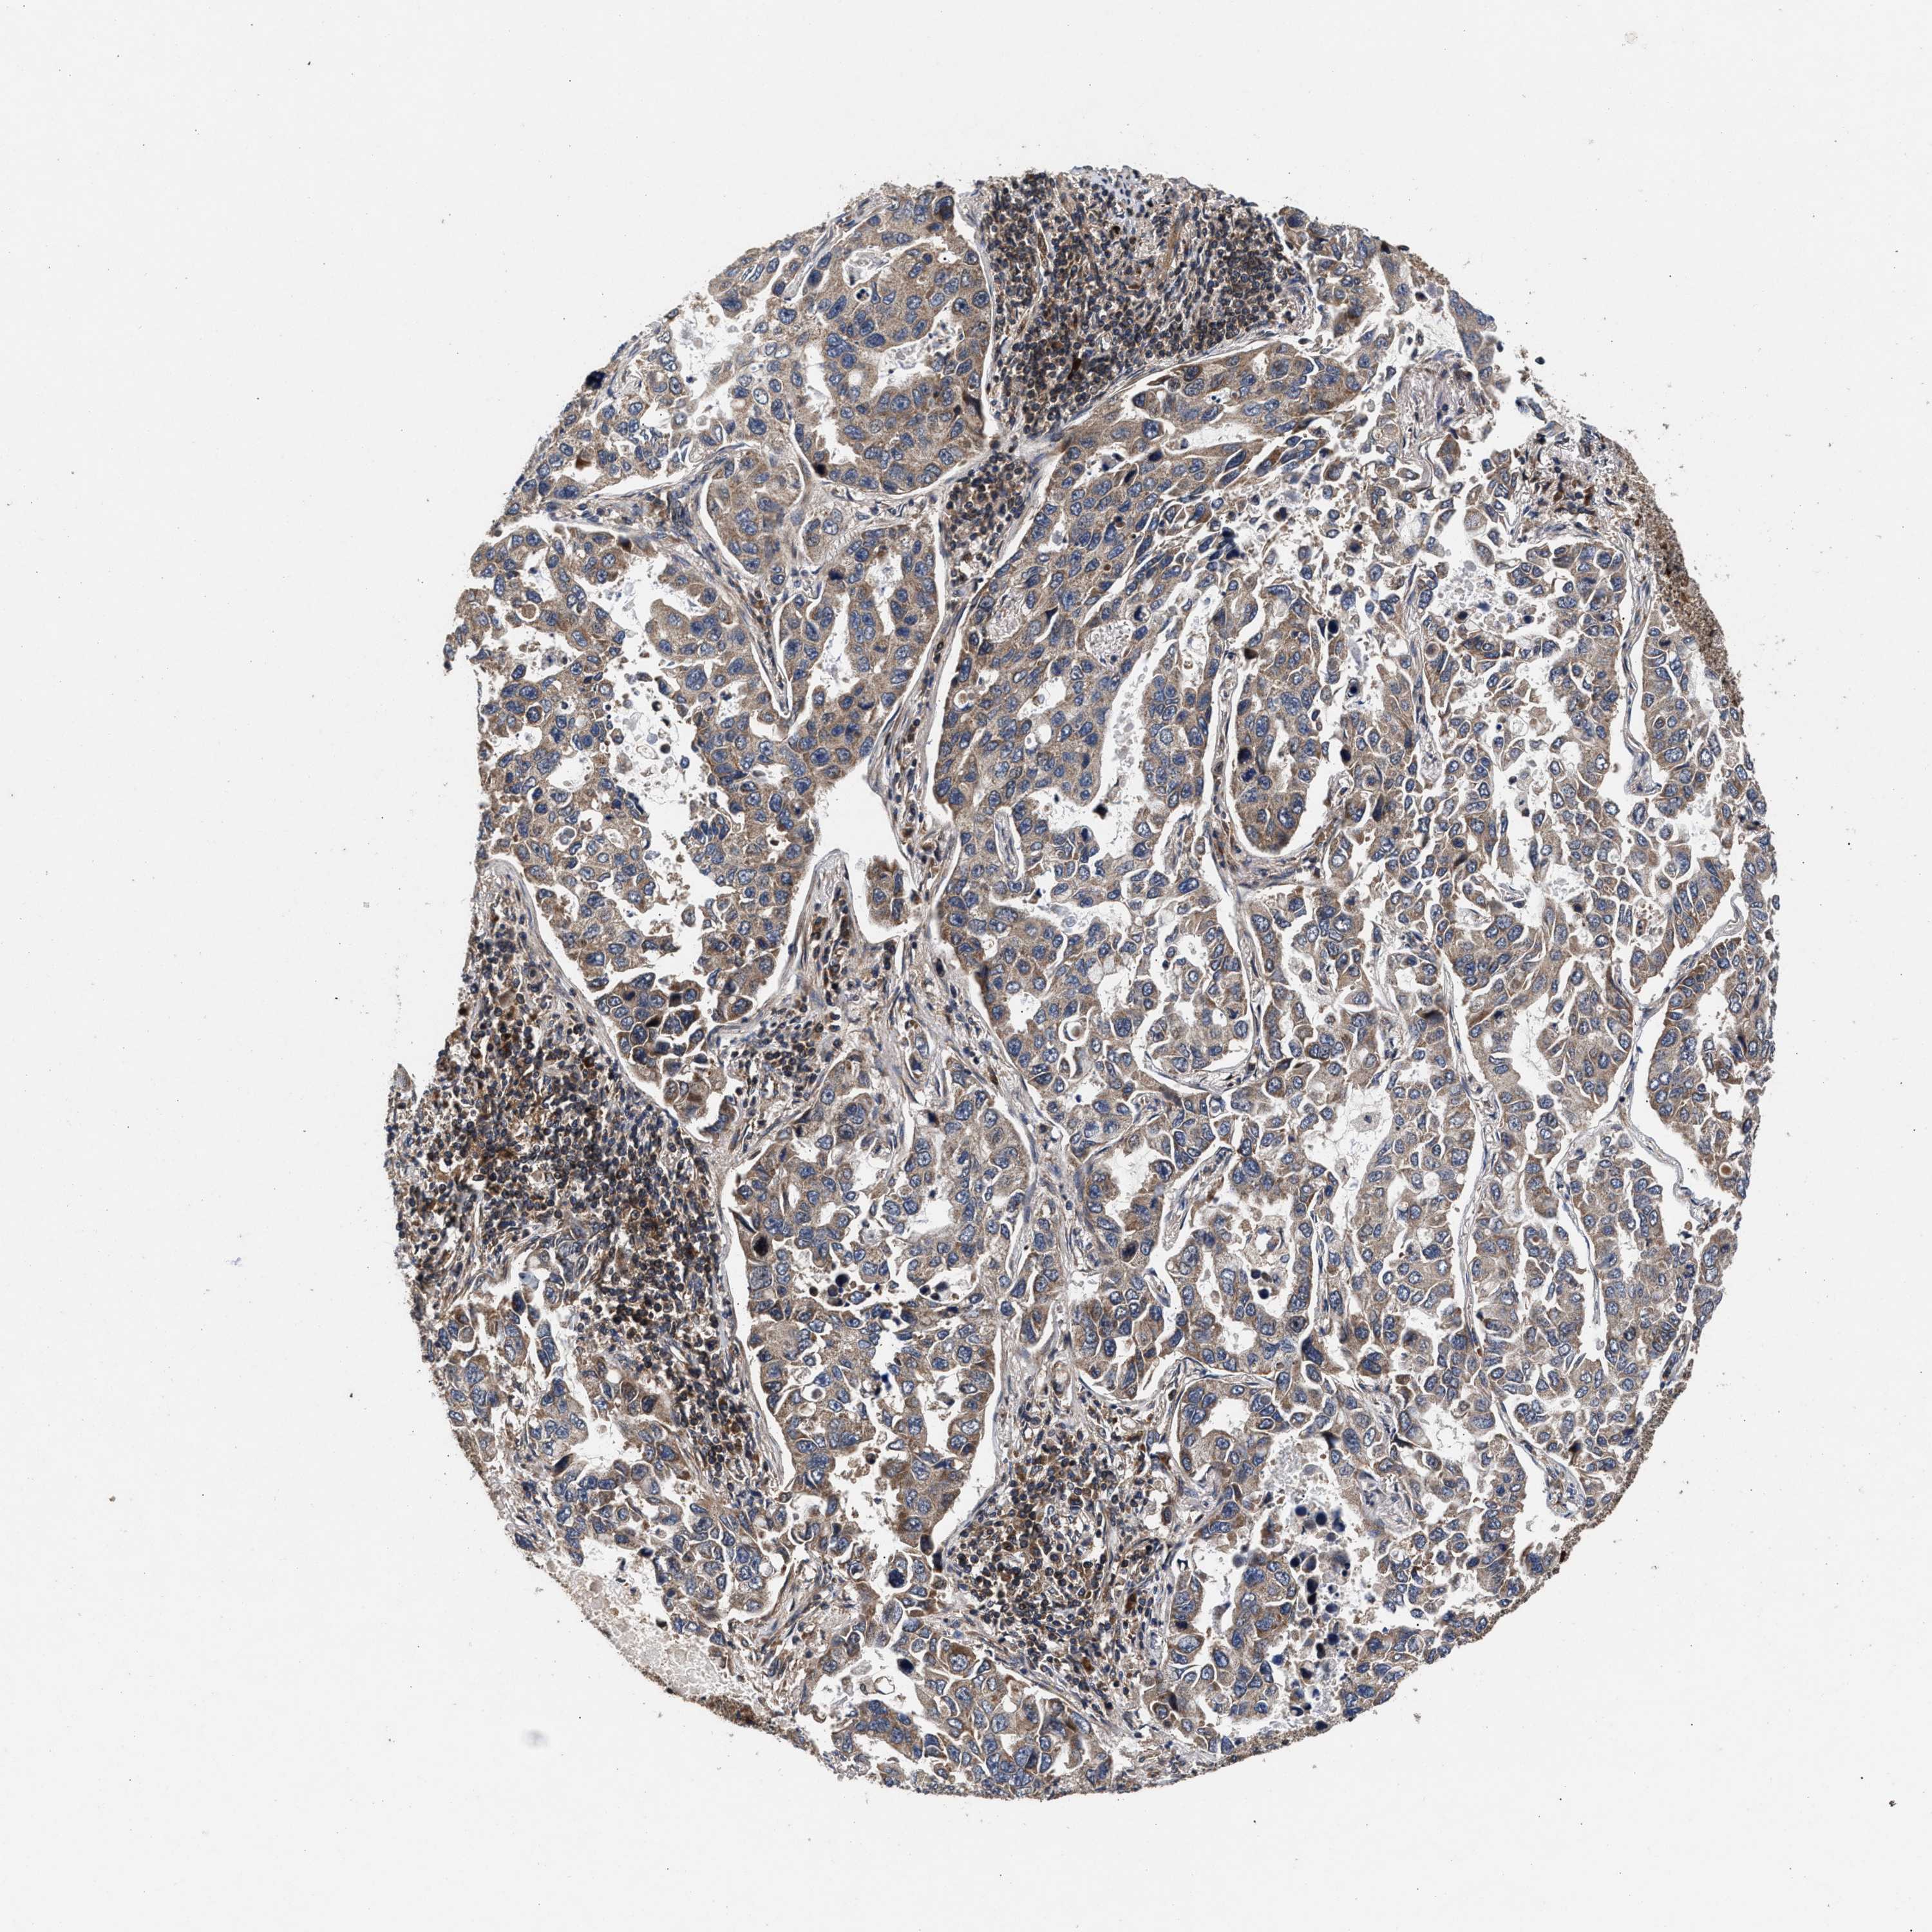

CANCER LUNG CANCER Show tissue menu

LUAD TCGA LUAD VALIDATION LUSC TCGA LUSC VALIDATION PROTEIN LUAD CPTAC PROTEIN LUSC CPTAC PROTEIN EXPRESSION